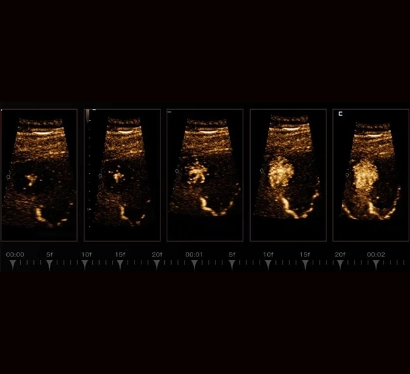

The topics in FAH-SYSU are discussed in small groups and one-on-ones in relation to future improved technologies. The two-day program was marked on a high note with the live streaming of interventional procedures of the liver, breast, and thyroid. With the MiCo+ ultrasound IT platform, over 20 doctors were able to view the ultrasound screen at the same time and discuss the procedures in different rooms through real-time audio and video transmission.

How the MiCo+ IT platform can work for ultrasound diagnosis, consultation and education has impressed and inspired further planning for doctors from afar. Similar to a virtual classroom, remote ultrasound education platforms enable healthcare professionals to access high-quality educational resources, participate in interactive training sessions to understand more types of diseases, and engage in real-time discussions with experts from around the globe. This has a special value for areas with limited education and medical resources, ultimately leading to improved patient care and outcomes on a global scale.

High-resolution ultrasound techniques like ZST+ and HiFR CEUS offer improved chances of early tumor detection and ultrasound-guided treatment. Fusion techniques will enhance imaging connectivity, while 3D techniques with fusion and navigation aim to elevate ultrasound-controlled robot-assisted surgical and interventional tumor treatments.

Our ongoing research focuses on CEUS parametric and perfusion analysis for the diagnosis and intervention of liver tumors, thyroid tumors, lymph nodes, and mammary tumors. Modern elastography techniques and initial applications of AI are also being explored, with the potential for multi-center studies. The M-Elite program serves as a foundation for effective training concepts for students, sonographers, and university research projects.